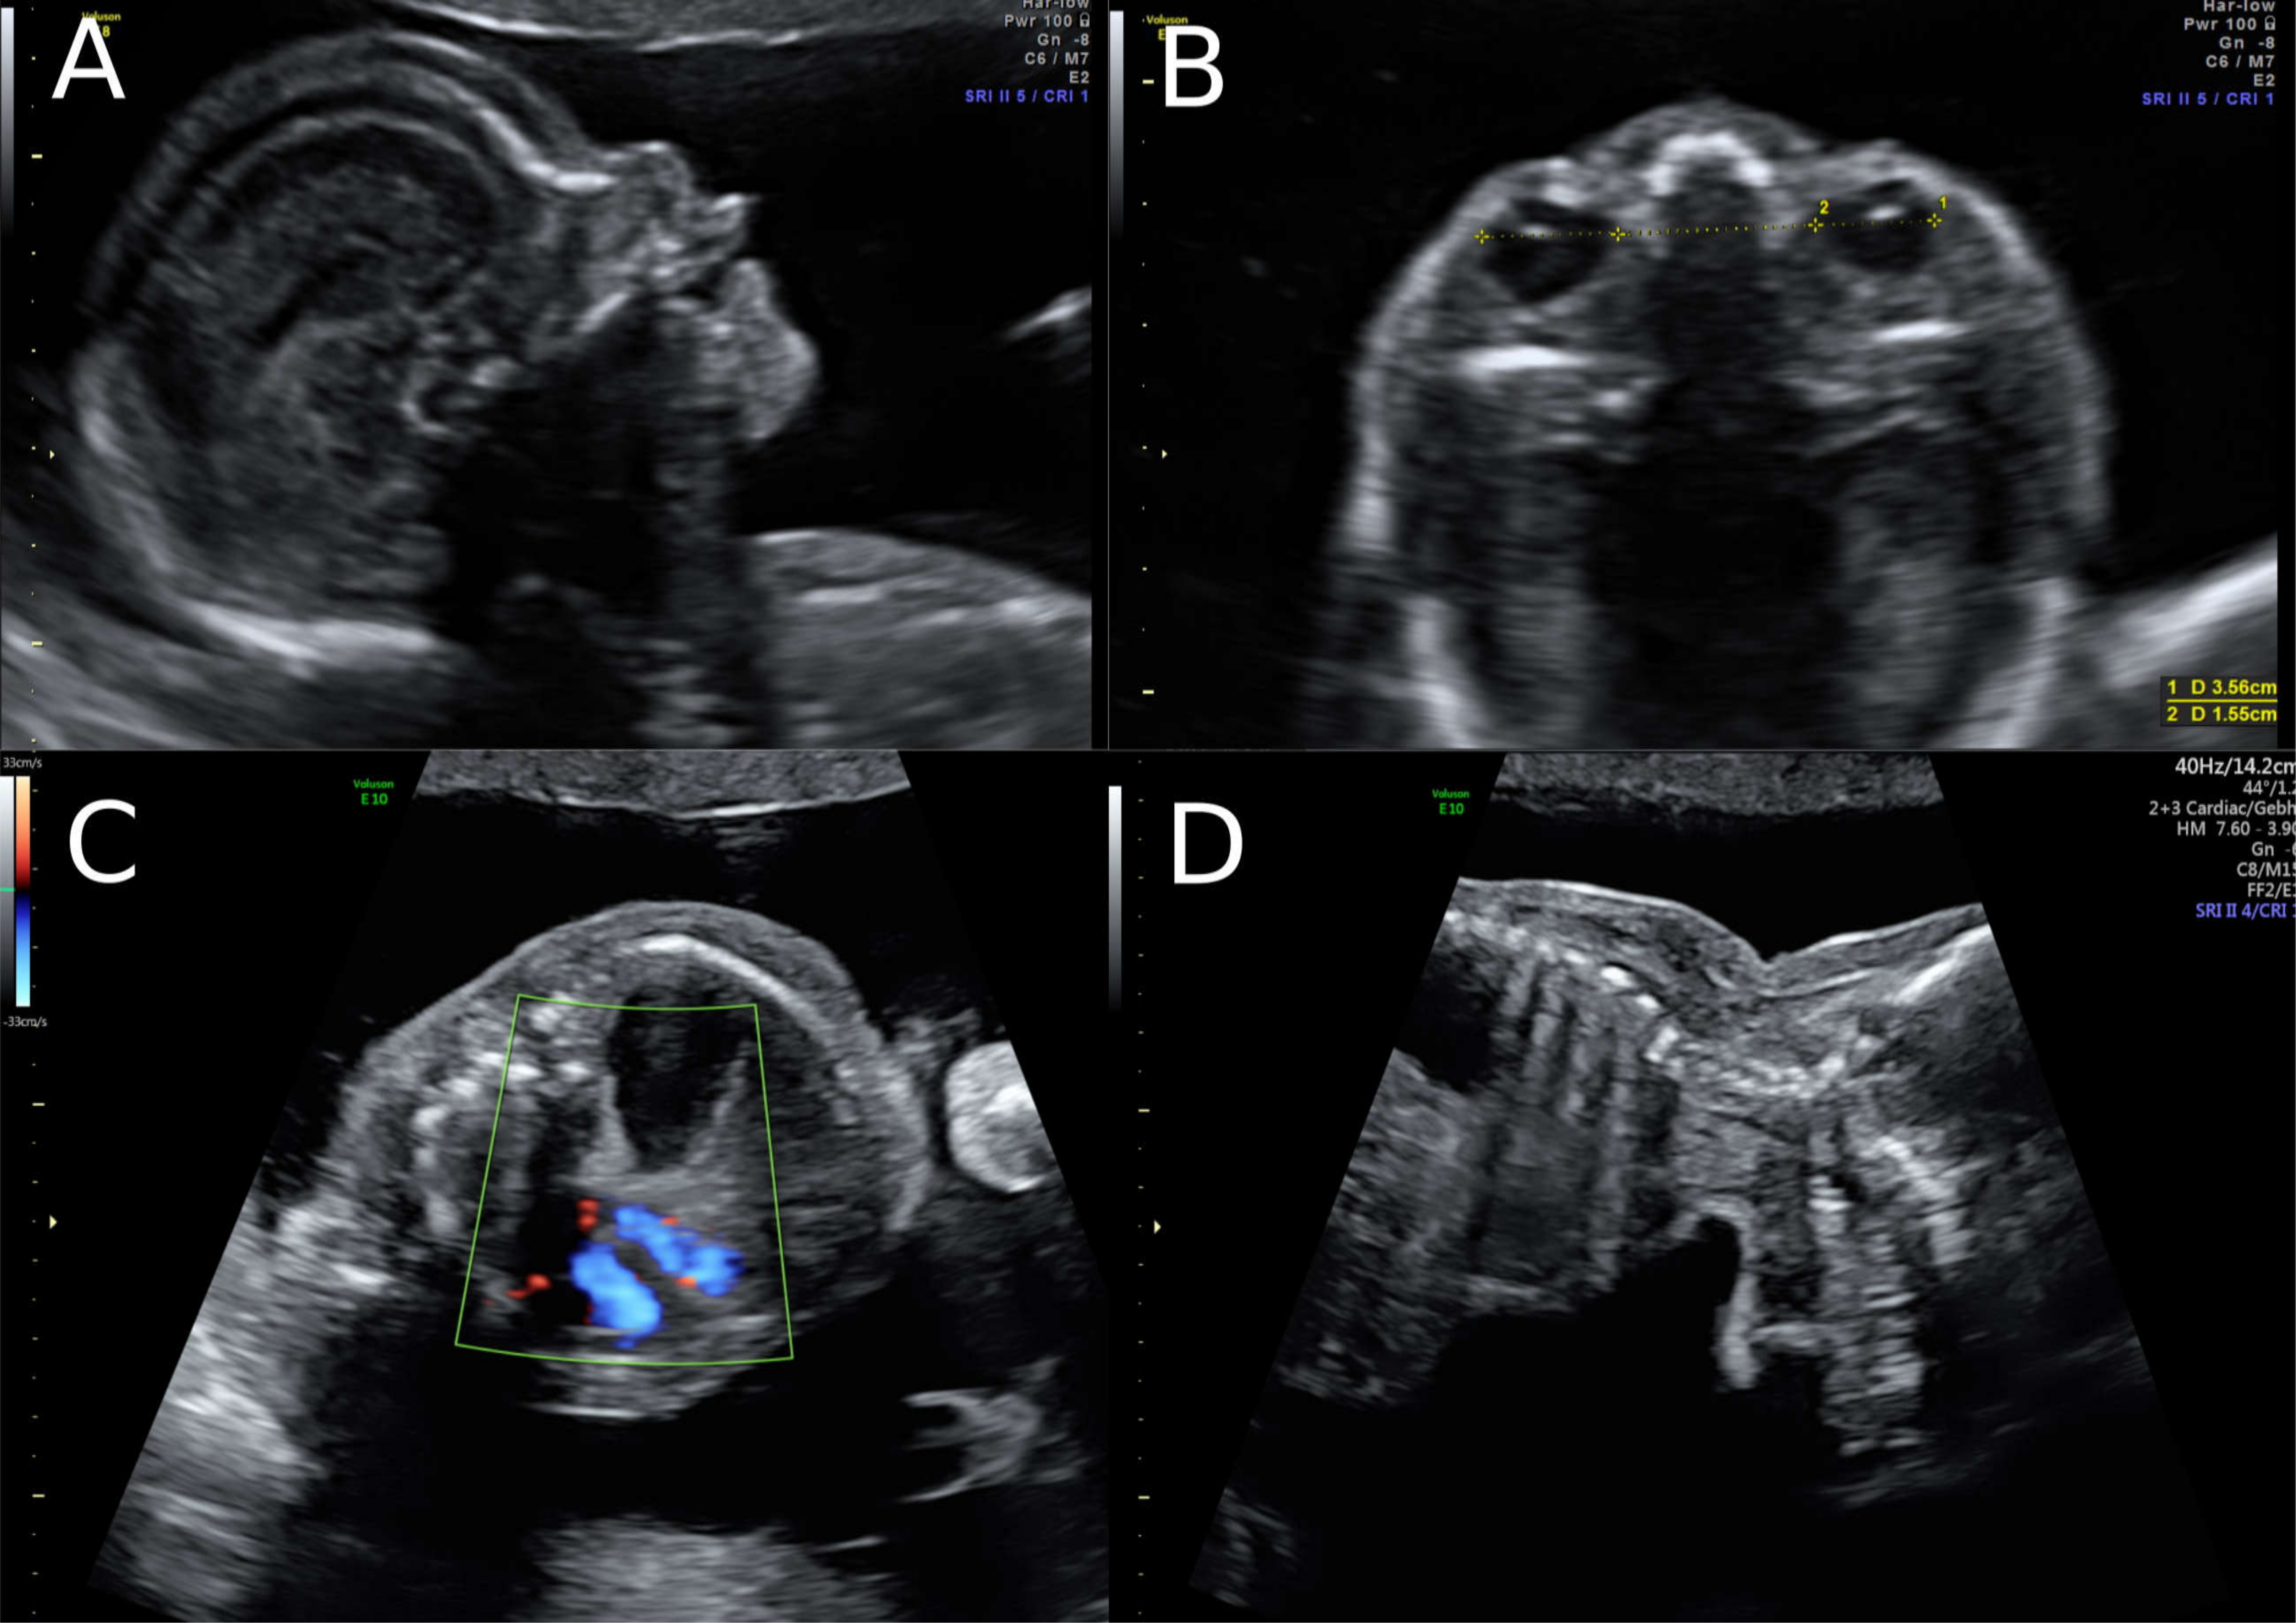

A 38-year-old women with a dichorionic-diamniotic twin pregnancy, after in-vitro fertilisation, attended routine first trimester screening at 13 + 4 weeks of gestation. One of the twins (fetus I) pair showed normal NT measurement and a low risk for chromosomal abnormalities, whereas the other twin (fetus II) presented an increased NT of 5.2 mm, the position of the fetal heart in the middle of the thorax, and hyperechogenic kidneys (Figure 1). At this stage, the patient declined invasive diagnosis. At 15 + 5 weeks of gestation, additional findings to the ones above, including hydronephrosis, skin oedema, and a right-sided clubfoot, have been observed. Subsequently, amniocentesis in the affected fetus was performed and revealed a 46, XY karyotype. Estimated fetal weight for both were average for the gestational age but abdominal circumference (AC) of the second twin was at the 95th percentile. At 22 + 0 weeks of gestation, the overall estimated fetal weight of fetus II was above the 95th percentile and a nuchal fold of 8.1 mm with general oedema of the skin was present. The ultrasound scan additionally showed a striking profile (Figure 2). All measurements (HC-AC-FL) were above the 95th percentile. A suspicion of left-sided diaphragmatic hernia as well as hyperechogenic kidneys, increased in size and polycystic appearance, and a hypoplasia of genitalia have been identified. Furthermore, the scan revealed a polyhydramnios (DIP 10 cm). Due to the polyhydramnios of fetus II, fetus I has been compromised in a similar process as twin-to-twin transfusion syndrome, although fetal development and amniotic fluid have been normal (Figure 3).

Figure 1. Ultrasound findings in the 1st Trimester. (A) Increased Nuchal Translucency (NT) at 13 + 5 weeks of gestation in twin II. (B) A simple cystic structure in the abdomen, most probably a gastrointestinal duplication cyst. (C) Hyperechogenic kidneys. (D) Malposition of the fetal heart in the chest at 13 + 5 weeks. The position of the fetal heart in the middle of the thorax.

Figure 2. Ultrasound at 22 weeks of gestation (A,B) Striking profile and brain structure in fetus with Simpson-Golabi-Behmel syndrome. (C) Suspicion of congenital diaphragmatic hernia at 22 weeks of gestation and (D) increased subcutaneous fat tissue.